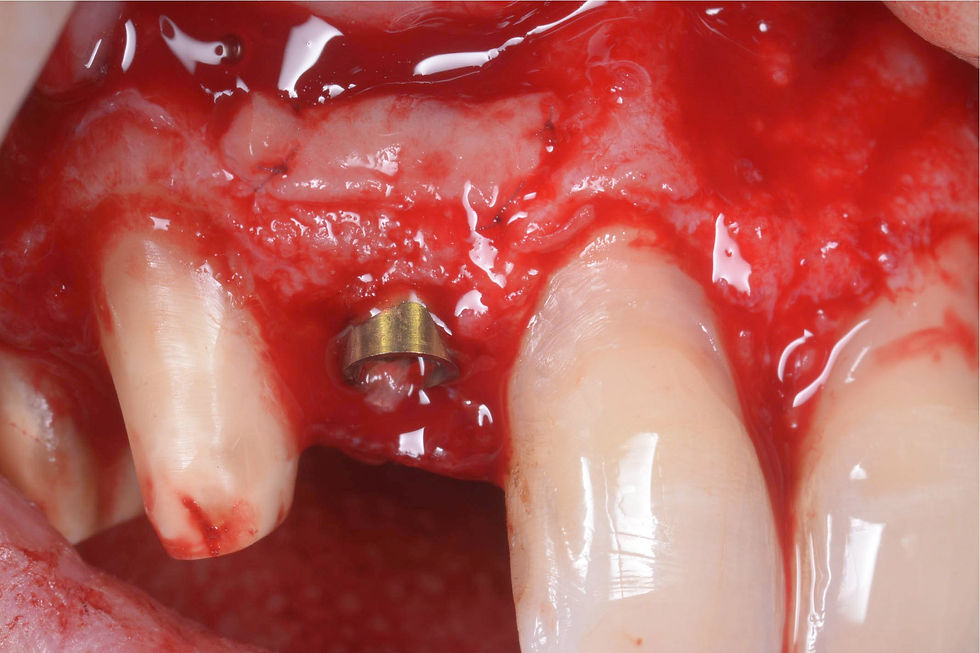

Insertion of Prama RF implant in a semi-submerged position: the endosseous morphology allows the implant to be kept very palatal and to minimize the impact on the vestibular wall, which is very thin in the apical area.